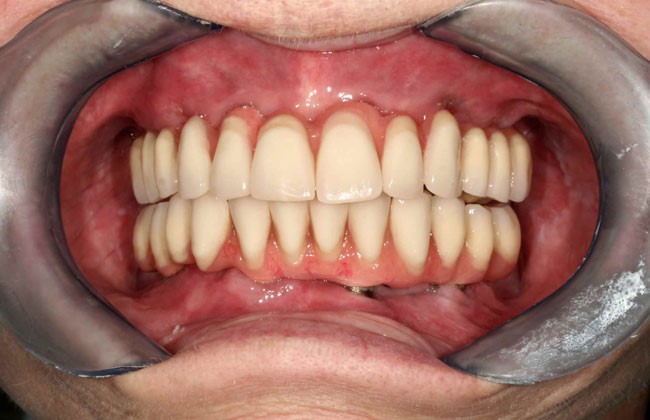

Minimálisan 3-4 hónap elteltével végleges implantátumokra csavarozható hídprotézis elkészítése csúcsminőségű CAD/CAM technológiával. Az elvesztett csont és lágyrészek esztétikus pótlása rózsaszín porcelánnal történik. A végleges fogpótlás anyaga többféle lehet, a választás a beteg esztétikai elvárásaitól függ.

A végleges fogpótlás elkészítésénél figyelembe vesszük az ideiglenes viselése során felmerülő igényeket és annak ismeretében változtatunk rajta. Ez a munkafolyamat is több fázisból áll: mintavétel, minta visszaellenőrzése, vázpróba, matt próba, harapás összecsiszolása, végleges hídprotézis felerősítése és a csavarbemenetek tömőanyaggal történő zárása. Elkészítés ideje minimálisan 2 hét, de ezen idő alatt az ideiglenesen korábban elkészült pótlást végig viselni tudja.

A képek csak illusztrációk (a szájról készült fényképen cocr vázra égetett porcelán pótlás látható) a munkafolyamatok és a fogpótlás szerkezetének könnyebb megértése érdekében. Az ön fogpótlása csak hasonlóan fog kinézni, csak a jellege ugyanilyen. A szürke csavarozható elemek a mélyben látszódhatnak, a rózsaszín íny és a fogak átmenete hasonló lesz, de az elveszett csont és lágyrészek mennyisége, az íny lefutása, az implantátumok helyzete, helye mindenkinél más így a pótlás kinézete is változik.